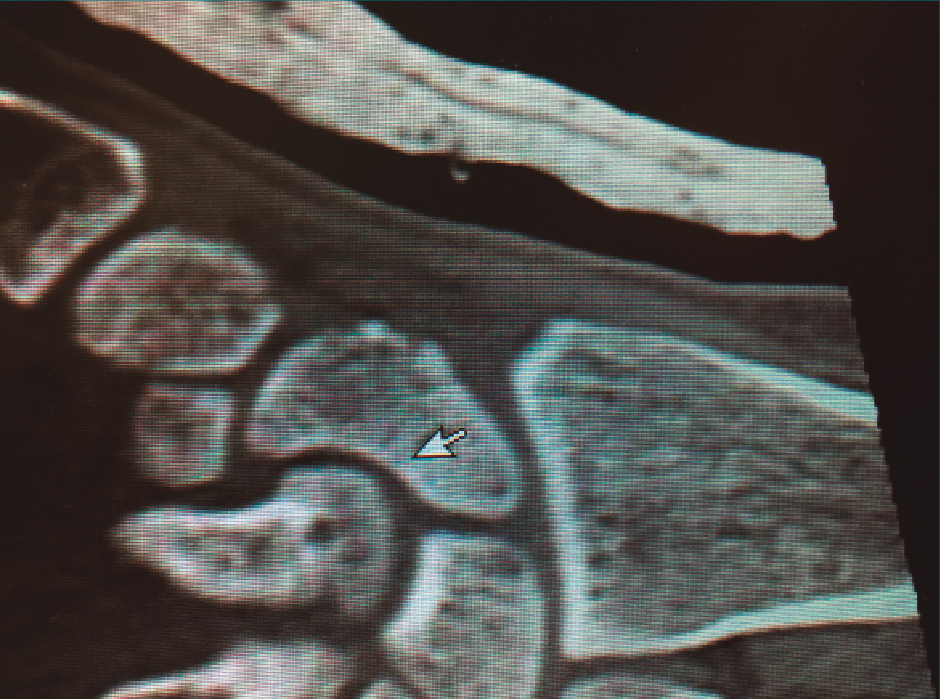

En cuanto al diagnóstico, la controversia reside en cuándo y qué pruebas complementarias realizar en las sospechas clínicas de fractura sin una imagen de radiología concluyente. A menudo las fracturas agudas pasan desapercibidas; la sensibilidad de la radiología va del 84 al 98%(1), la resonancia magnética nuclear (RMN) puede ser útil, con una sensibilidad superior al 95%, pero con una especificidad inferior(2), siendo la tomografía computarizada (TC) la más sensible y especifica(3)(Figura 1).

Figura 1. Imagen de fractura no desplazada de escafoides en tomografía computarizada.